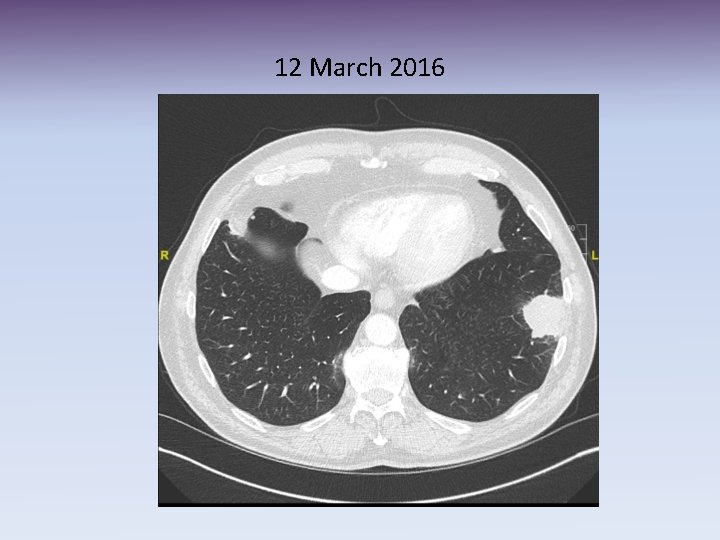

12 March 2016